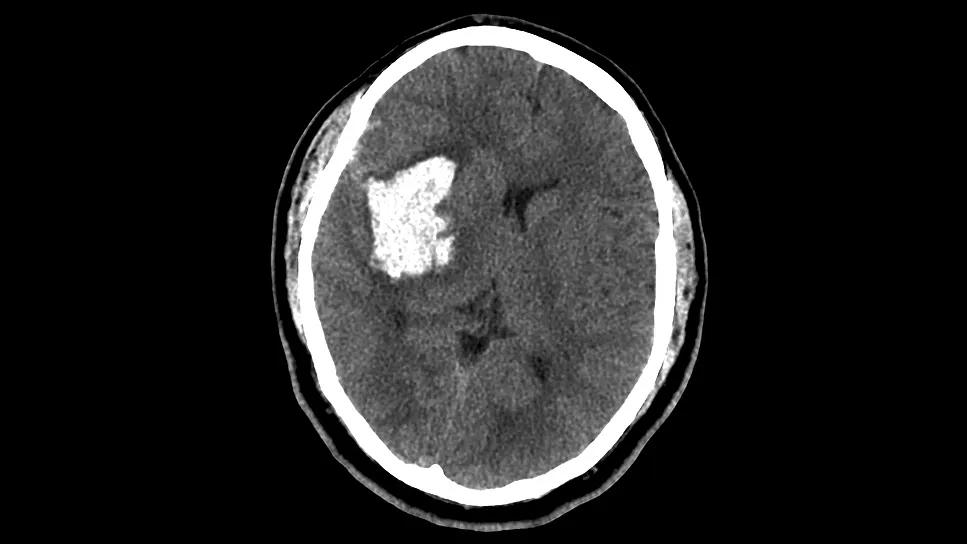

brain scan showing hemorrhage in the putamen

A Cleveland Clinic study focused exclusively on moderate-size putaminal intracranial hemorrhages (pICHs) has challenged previous notions about the efficacy of minimally invasive surgical (MIS) evacuation in this difficult-to-treat patient population. The findings, published in the Journal of Neurosurgery, suggest that MIS evacuation of pICHs from 10 to 50 mL in volume is associated with significantly lower one-year mortality and a shorter ICU length of stay (LOS) compared with maximal medical management.

Putaminal ICH is a subtype of basal ganglia ICH (bgICH). While prior large-scale trials have shown limited or neutral results for bgICH management, this single-center study using propensity matching provides unique insights into which patients with pICH are most likely to benefit from surgical intervention based on the hemorrhage’s precise spatial distribution. The study also introduces a method of volumetric imaging analysis, easily accessible via routine CT, that could be integrated into clinical workflows to triage management strategies and identify ideal surgical candidates.